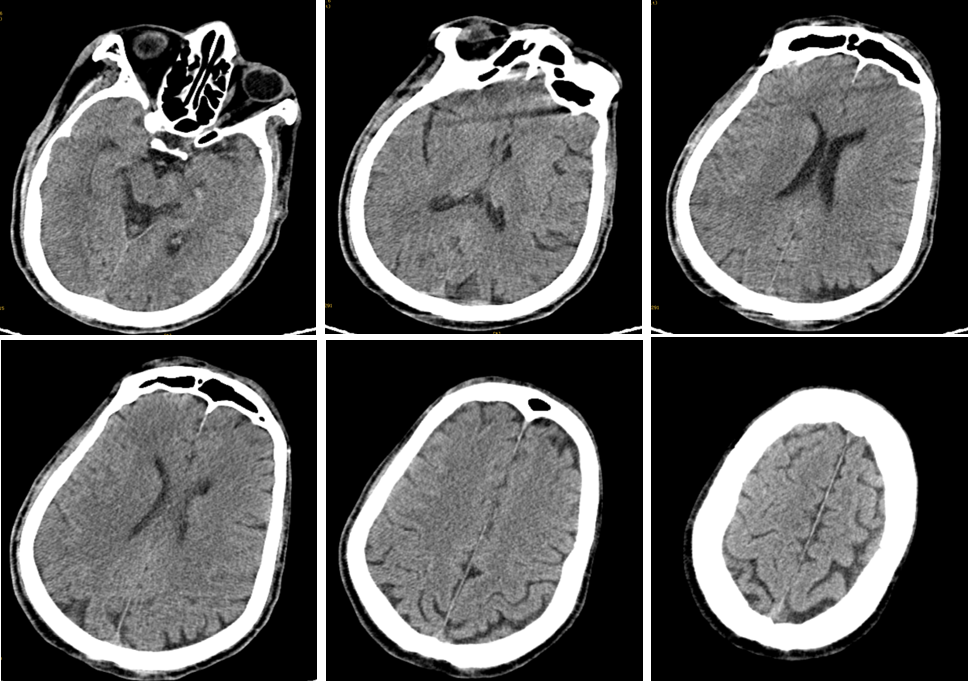

简介:男,72岁,2018年6月22日入院。

主诉:左侧肢体乏力、言语不清5小时。

体查:神清,构音不清,左眼外展受限,左侧肢体肌力2级,左侧巴氏征(+)。

评分:ASPECTS 10分 NIHSS 11分。

病史:发病前mRS:0;否认慢性病史。

心电图示:1. 心房颤动;2. T波改变;HR 66次/分。

发病5.5小时开始手术。

事件:M1中远段闭塞